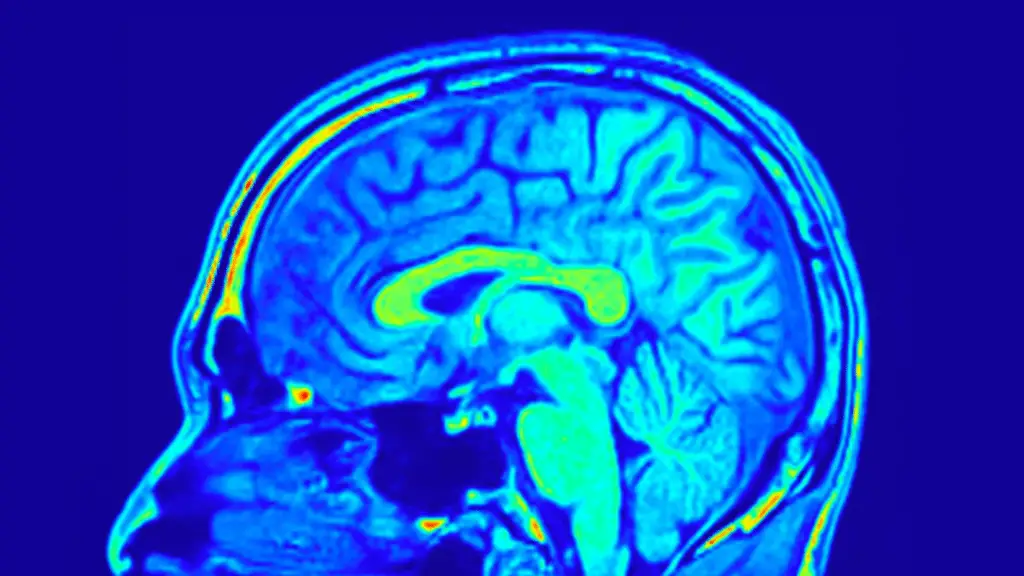

Il ruolo chiave del cervello (e della risonanza magnetica)

La parte più innovativa dello studio riguarda però la risonanza magnetica cerebrale (MRI). Analizzando la struttura del cervello, i ricercatori hanno individuato reti neurali specifiche in grado di prevedere quanto un paziente avrebbe beneficiato del trattamento.

Alcune di queste reti risultavano predittive in entrambi i gruppi, ma altre erano specifiche solo per chi assumeva Yueju Pill. In particolare, contavano parametri come:

- spessore corticale

- profondità dei solchi cerebrali

Entrambi sono indicatori legati allo sviluppo e al funzionamento del cervello.

Un dato curioso e inatteso riguarda la rete visiva: questa area del cervello si è rivelata particolarmente importante nel prevedere sia il miglioramento dei sintomi depressivi sia l’aumento dei livelli di BDNF nei pazienti trattati con Yueju Pill.